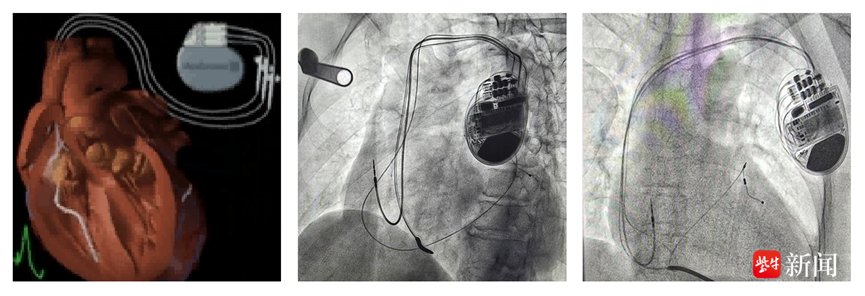

影像图

据介绍,CRT-D术结合了CRT(心脏再同步化治疗起搏器)和ICD(埋藏式心脏自动除颤器)的双重功能,最大的特点是在治疗心脏功能衰竭、让扩大的心脏回缩的同时,防止因恶性心律失常导致的猝死,主要适用于完全性左束支伴心肌病或冠心病合并心衰及有猝死高危风险的患者。

房室结消融术的目的是消除房颤自身不规则且快速的电信号干扰、抑制CRT-D的起搏指令。消融后这种干扰被彻底消除,CRT-D能时刻掌控心跳,实现最理想的同步治疗。